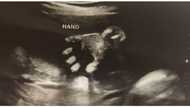

Imbis na matuwa para sa buntis na magsisilang ng isang supling sa mga susunod na buwan, kinuwestiyon at pinangaralan ng isang netizen ang ina dahil pandemya.